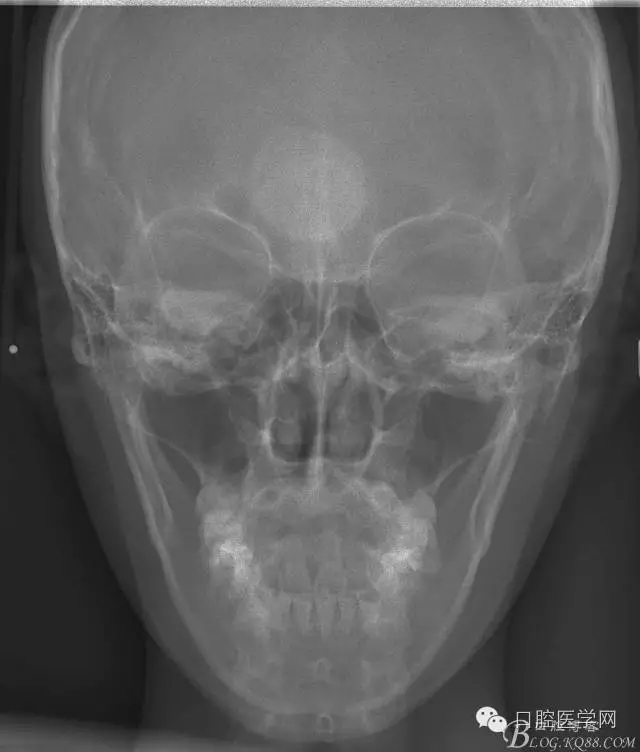

患者,女,13歲。要求矯治排齊上下前牙。

查:右側(cè)第二前磨牙第一乳磨牙恒尖牙頰側(cè)前庭溝隆起,捫有乒乓球感。曲斷及CT示:右側(cè)第二前磨牙第一乳磨牙恒尖牙根尖區(qū)有一囊腫,頰舌側(cè)骨板極薄,牙根無吸收,第二前磨牙牙根位于囊腫中,第一雙尖牙牙冠遠(yuǎn)中水平向阻生,牙冠位于囊腫中。經(jīng)協(xié)議:手術(shù)摘除創(chuàng)傷大,同意開創(chuàng)引流保守治療。

正畸查:替牙合。第一恒磨牙中性合。上牙弓尖圓型下牙弓方圓型。前牙覆合3度覆蓋7.5mm。下前牙咬到上舌側(cè)牙齦。上頜擁擠4.0mm,下頜擁擠

3.0mm。上頜稍前突下頜后縮,上下唇前突,上前牙覆蓋下唇,下唇外翻。面下三分之一過短,頦唇溝明顯,開唇露齒,頦饜窩明顯。顳下頜關(guān)節(jié)開閉口無彈響,無壓痛,開口型開口度正常。